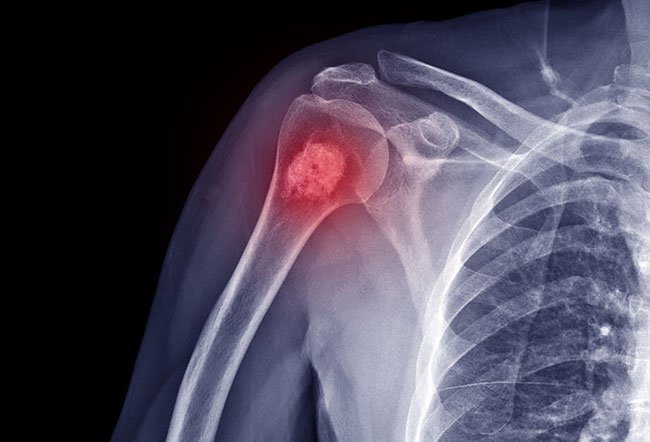

An aneurysmal bone cyst (ABC) is a non-cancerous bone tumor (abnormal growth) found in less than 1 in 100,000 children and adolescents per year. The majority of ABCs are liquid-filled cysts, or blood-filled sacs, making them fragile and at risk of fracturing. How to treat an aneurysmal bone cyst depends on the symptoms and circumstances of each unique case.

An aneurysmal bone cyst is a destructive bone tumor, or a liquid or blood-filled sac. 70% of aneurysmal bone cysts occur in people who have no other diseases. The other 30% occur in people who already have other bone lesions (organ or tissue damage) or tumors.

- X-ray, which creates images of the bone